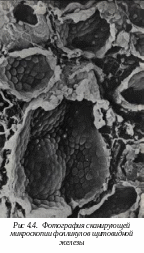

4.4. Микроскопическое строение щитовидной железы

Щ

итовидная железа состоит из двух долей, соединенных перешейком. Снаружи щитовидная железа покрыта двумя капсулами: первая служит продолжением перитрахиальной фасции (глубокой фасции шеи), вторая - истинная соединительно-тканная. Внутрь от капсулы отходят перегородки, образуя опорный аппарат железы, по которому в железу идут кровеносные сосуды и нервы. Так как перегородки не соединяются, паренхима железы не разделена до конца на дольки - железа имеет псевдодольчатое строение.

Гормоны щитовидной железы (Т3 и Т4) регулируют уровень основного обмена, а кальцитонин участвует в поддержании нормального уровня кальция в крови. Соответственно в ее паренхиме выделяют два типа клеток: фолликулярные эндокриноциты - тироциты, и парафолликулярные эндокриноциты - кальцитониноциты.

Т

ироциты формируют стенку фолликула и являются основной морфофункциональной единицей щитовидной железы. В железе около 30 млн. фолликулов, диаметром от 0,05 до 0,5 мм, окруженных базальной мембраной. Тироциты синтезируют тироксин и трийодтиронин. Образование гормонов тироцитов проходит ряд стадий.